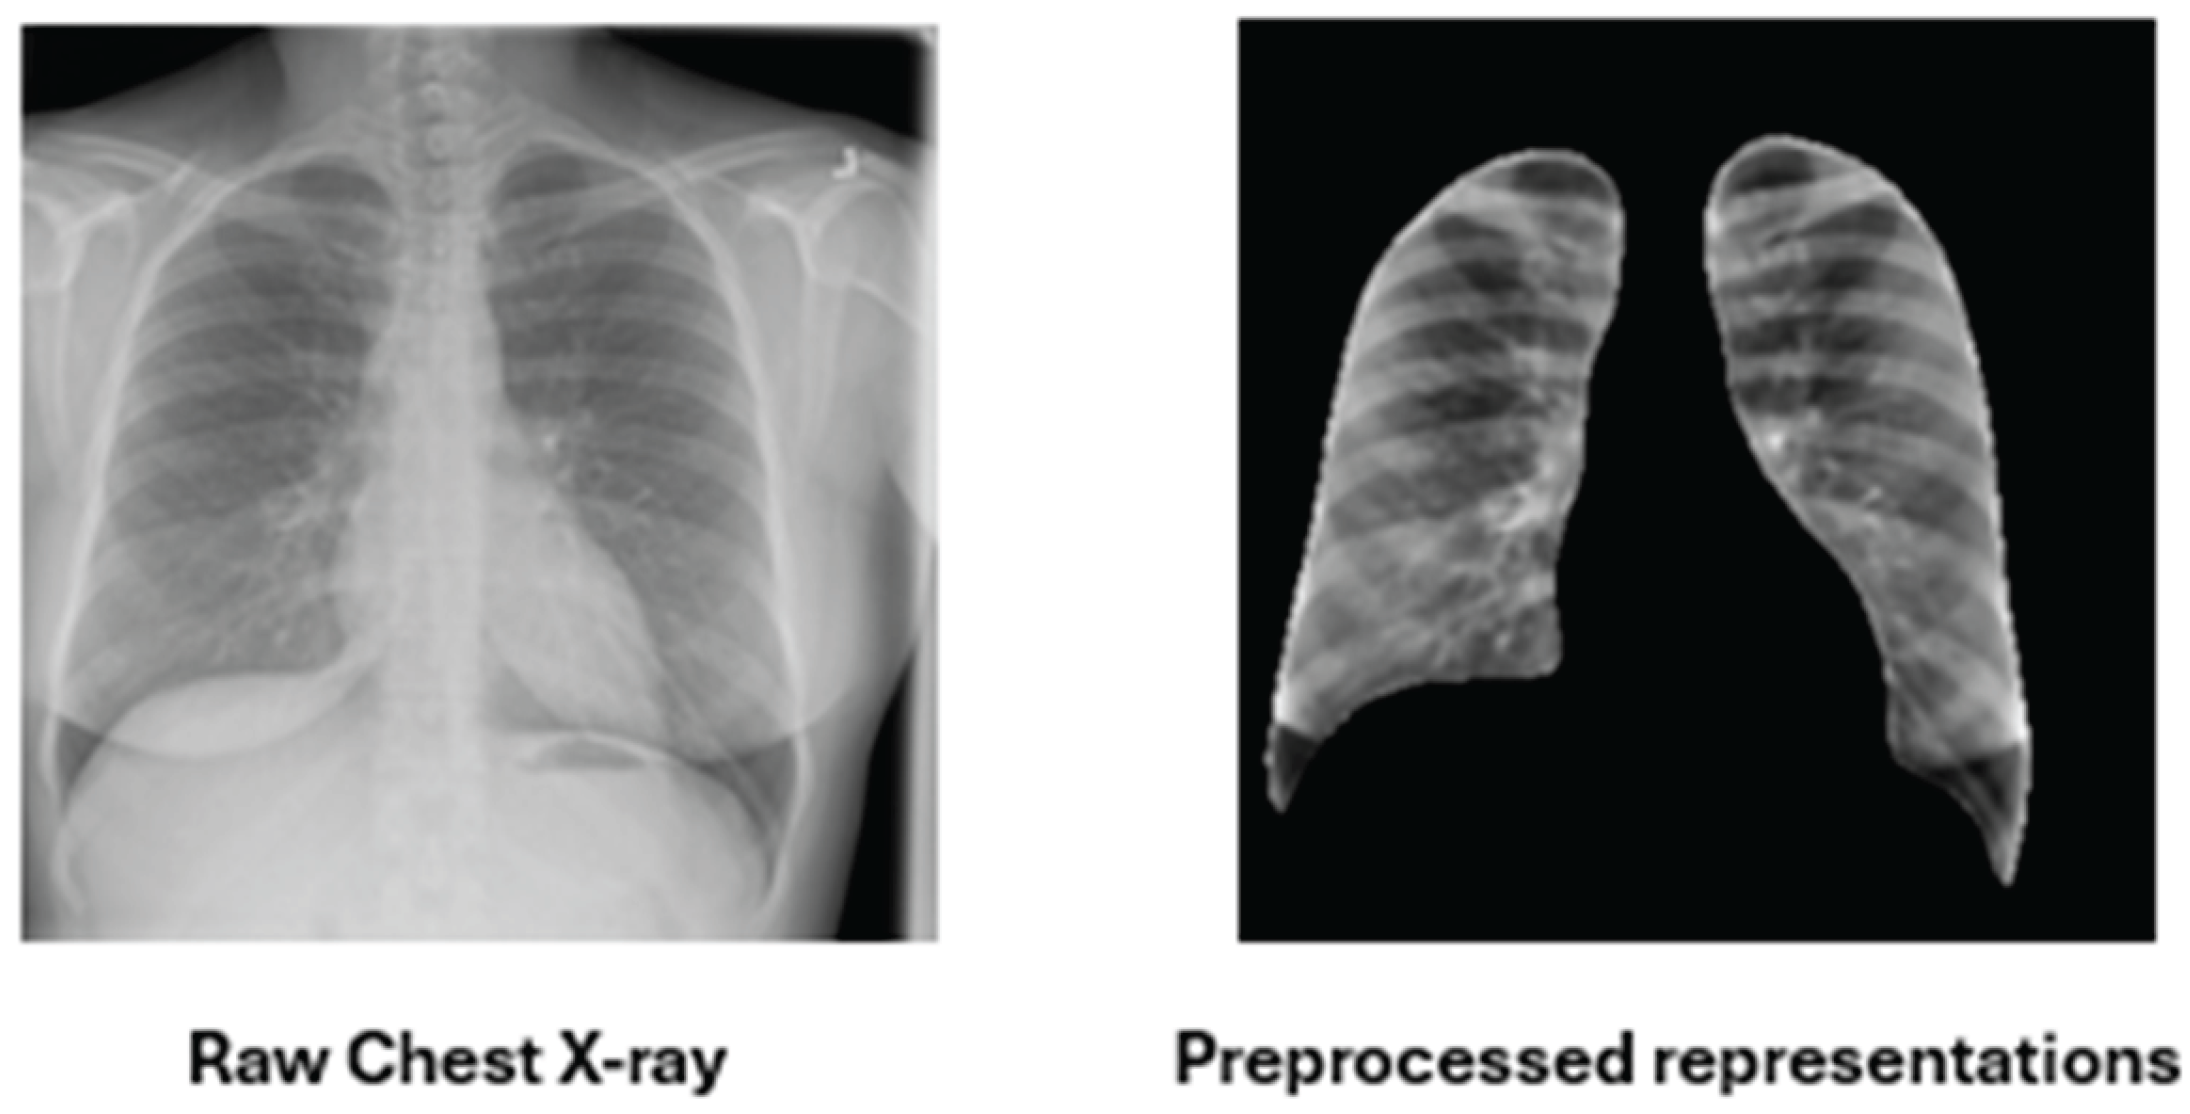

3.1.1. Pulmonary Region of Interest (ROI) Extraction

- Lung Region Isolation

- Soft-Tissue Enhancement: CLAHE and Bone Suppression

3.1.2. Multi-Channel Feature Construction